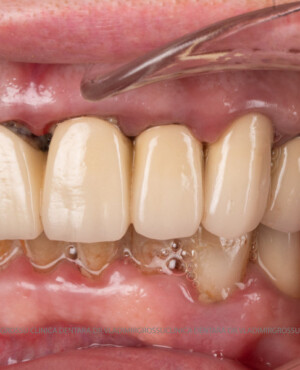

Caz 1